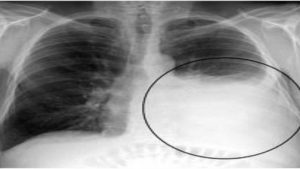

Giãn phế quản là một bệnh lý thuộc chuyên khoa hô hấp. Bệnh gây tổn thương trực tiếp đến phế quản, đường dẫn khí trong phổi, có thể dẫn tới nhiều biến chứng đáng lo ngại. Hãy cùng Docosan tìm hiểu về triệu chứng và các cách điều trị giãn phế quản trong y học […]